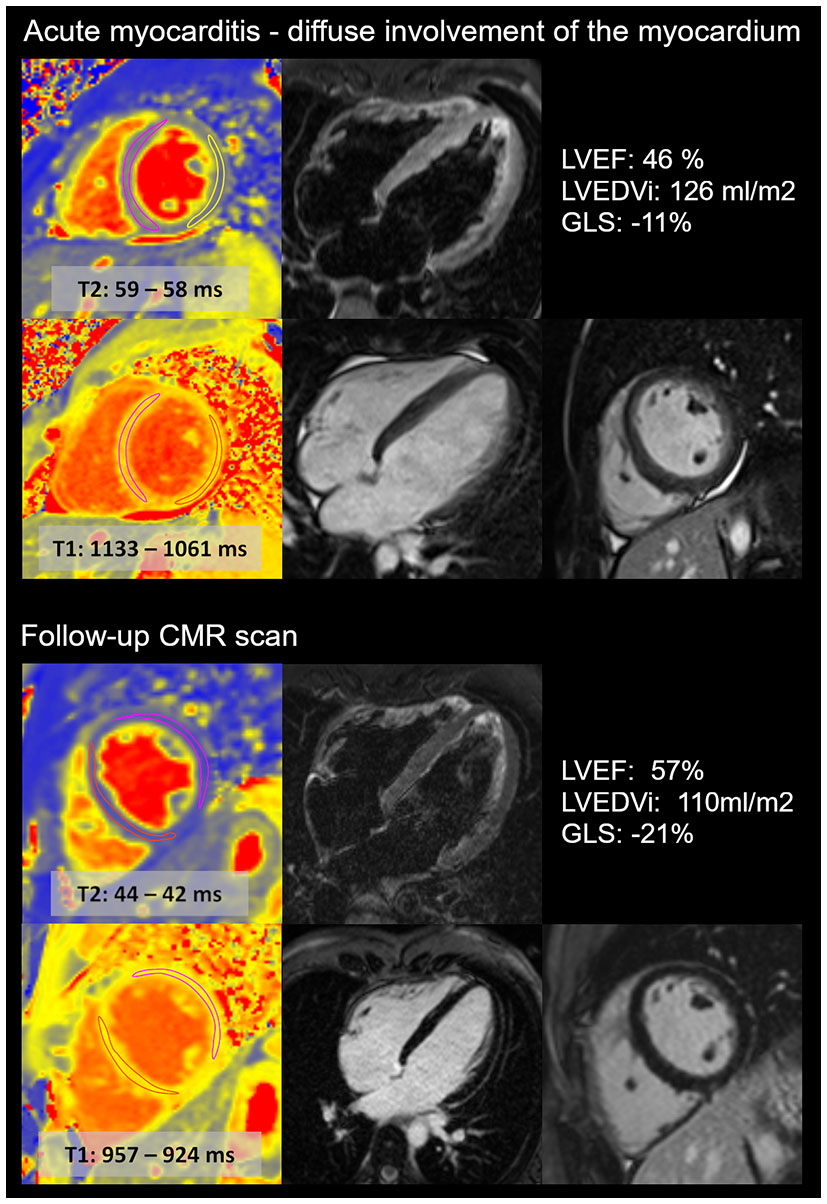

CMR was performed on average 4 ± 2 days (between 1 and 8 days) after the onset of acute chest pain. The majority of the cases showed a localized pattern of myocarditis, mainly affecting the lateral wall of the left ventricle with signs of subepi-midmyocardial oedema and necrosis (Figure 2). In one case, we found diffuse myocarditis with elevated T2, T1 and ECV values (Figure 3) caused by the mRNA vaccine. The left ventricular ejection fraction (LVEF) was in the normal range for most cases, except for two patients whose LVEF was mildly decreased (46 and 47%). Notably, these two patients had no previous history of acute myocarditis. There was no definitive pericardial involvement in any patients.

Figure 3

Diffuse acute myocarditis after the second dose of anti-COVID-19 mRNA vaccine in a young athlete. CMR images show the acute (upper images) and follow-up (lower images) scans of a young, highly trained athlete (national team member). The first CMR scan confirmed acute myocarditis with diffuse involvement of the myocardium, with elevated T2 and T1 mapping and diffuse myocardial oedema. The left ventricular ejection fraction (LVEF) was mildly decreased, and global longitudinal (GLS) strain was decreased during the acute scan. The follow-up scan revealed the normalization of T2 and T1 mapping values and left ventricular systolic function. The LVEDVi decreased. No LGE was present. The patient was prohibited from participation in sports activity for the first 3 months, and then he gradually returned to sports activity. Currently, the athlete performs a high level of sports activity and does not report recurrent or persisting symptoms.

Clinical status and CMR changes during follow-up

During our follow-up, one patient experienced a recurrent episode of acute myocarditis (3 months after the vaccine), preceded by gastrointestinal infection. Other patients did not report symptom recurrence. The hs Troponin T (6[4, 7] ng/L), CKMB (2[2, 11] U/L), CRP (2[1, 3] mg/L) and proBNP (29[12,49] pg/ml) values returned to the normal range. Follow-up CMR was carried out 112 ± 27 days after the baseline scan (n = 14). We found that the LVEF marginally increased upon follow-up, and LVEDVi slightly decreased, both remaining in the normal range (Table 3). Elevated T2 values depicting local oedema in the affected area were resolved. The native T1 value and ECV measured in the affected area also decreased; however, ECV remained slightly elevated. The LGE area shrank in all participants and disappeared completely in 31% (4/13) of cases. The highly trained athlete in whom all signs of acute myocarditis disappeared on follow-up (Figure 3) was able to gradually return to sports activity. He restarted exercising 3 months ago and did not experience recurrent or persisting symptoms.